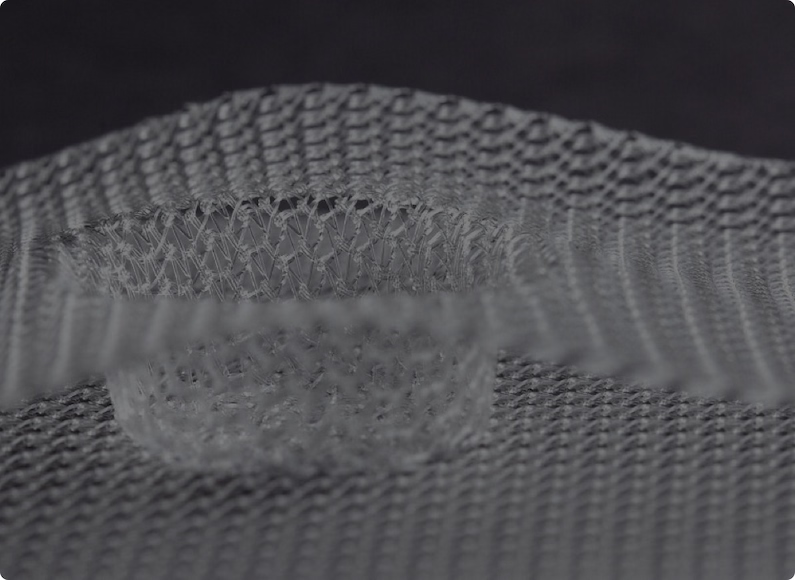

Le PLA/PCL 70 :30 ou POLY(L-LACTIDE-CO-Ε-CAPROLACTONE) 70:30 est un thermoplastique semi-cristallin, semi transparent et possède un aspect légèrement blanc. Il se résorbe entre 12 à 24 mois une fois implanté. Bien que cristallin le polymère à une température de transition vitreuse proche de la température ambiante, ce qui lui garantit une grande souplesse. Ainsi cette matière est généralement utilisée pour faire des renforts pariétaux, des guides de reconstruction nerveuse.